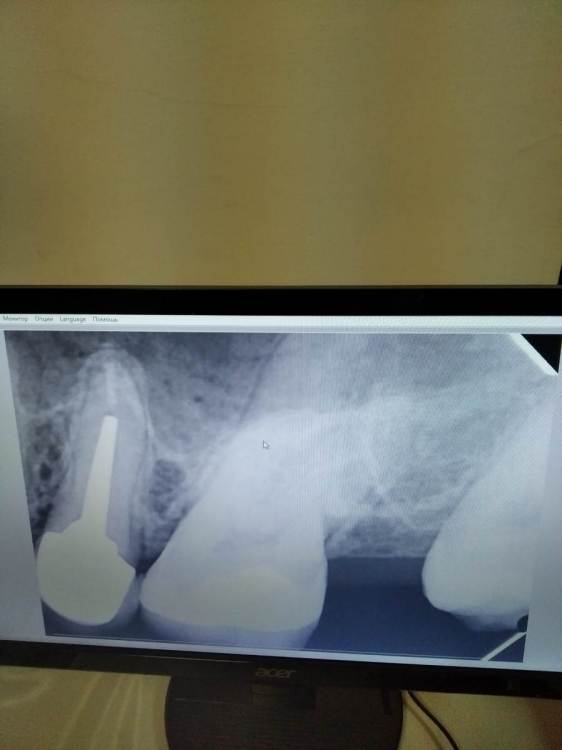

Елена8 Опубликовано 24 января, 2022 Поделиться Опубликовано 24 января, 2022 Добрый день) Скажите, пожалуйста, что это? Извиняюсь, я сфотографировала. По-другому там не получалось. У меня уже несколько недель болят зубы. Началось почему-то все после ОРВИ. Вначале было ощущение, что болит вся верхняя челюсть и отдает в лицо. Боли были ноющие, начинались под вечер. Сходила к одному стоматологу. Она сказала, что что-то с деснами в зубе мудрости и положила туда лекарство. А у меня как болело - так и продолжало болеть. Пошла к другому стоматологу. И вот она просто никак не может понять причину... Другим врачам при мне показывала снимки - никто ничего не знает, не понимает... КТ не могу скинуть. Своими словами скажу. Там кариес двух зубов, который при обычном осмотре не видно. Но как врач мне сказала - он далеко от нерва. В итоге она сказала, что у меня болезненные карманы. Их два. И вот она уже второй раз кладет лекарство в один из них. Один раз она это делала с анестезией, второй раз - без. Боль просто дикая... После лекарства картина поменялась. Теперь болит не все время. Но сильные боли тоже бывают. И как мне кажется - сейчас боли не ноющие, а дергающие. Вначале пила нимесил, но его долго нельзя. Теперь, когда болит, найз пью. Сегодня врач отправила меня к пародонтологу. Сказала - пусть он исключит со своей стороны. Если там ничего нет - она будет удалять нерв. Она меня просто замучила уже. Помогите, пожалуйста. На снимках видно что это? Ссылка на комментарий

Елена8 Опубликовано 26 января, 2022 Автор Поделиться Опубликовано 26 января, 2022 Сегодня снимки посмотрела пародонтолог. Сказала, что это и карман, и кариес 6-го зуба. А с ее стороны все нормально. Сейчас уже ничего не болит. Смотрите, у меня такой вот вопрос. Я запишусь кариес лечить. А с карманом нужно делать что-то? Его лечат как-то? Мне сказали только полоскать и пользоваться зубной нитью. А врач может что-то сделать? И будет ли он дальше болеть, если от лекарства он болеть перестал? Ссылка на комментарий